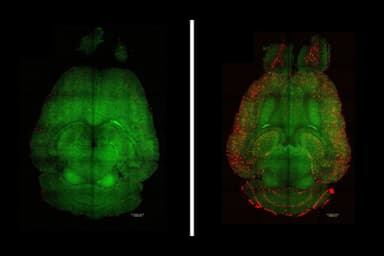

Để giải quyết thách thức này, nhóm nghiên cứu do Giáo sư Takuya Takahashi từ Trường Y thuộc Đại học thành phố Yokohama, Nhật Bản, dẫn đầu đã đạt được bước đột phá quan trọng. Như trình bày trong bài báo của họ đăng trên tạp chí Brain Communications ngày 1 tháng 10 năm 2025, nhóm đã giả thuyết rằng bệnh nhân sương mù não có thể biểu hiện sự thay đổi bất thường về biểu hiện thụ thể AMPA (AMPAR) – những phân tử then chốt cho trí nhớ và học tập – dựa trên các nghiên cứu trước về các rối loạn tâm thần và thần kinh như trầm cảm, rối loạn lưỡng cực, tâm thần phân liệt và sa sút trí tuệ. Do đó, họ đã sử dụng phương pháp mới mang tên [11C]K-2 AMPAR PET imaging để trực tiếp quan sát và định lượng mật độ AMPAR trong não người sống.

Bằng cách so sánh dữ liệu hình ảnh từ 30 bệnh nhân COVID kéo dài với 80 người khỏe mạnh, các nhà nghiên cứu phát hiện mật độ AMPAR tăng rõ rệt và lan rộng trong não của nhóm bệnh nhân. Mật độ receptor tăng này có tương quan trực tiếp với mức độ suy giảm nhận thức của họ, cho thấy mối liên hệ rõ ràng giữa thay đổi phân tử và triệu chứng. Ngoài ra, nồng độ các chỉ dấu viêm khác nhau cũng tỷ lệ thuận với mức AMPAR, gợi ý sự tương tác giữa viêm và biểu hiện receptor.